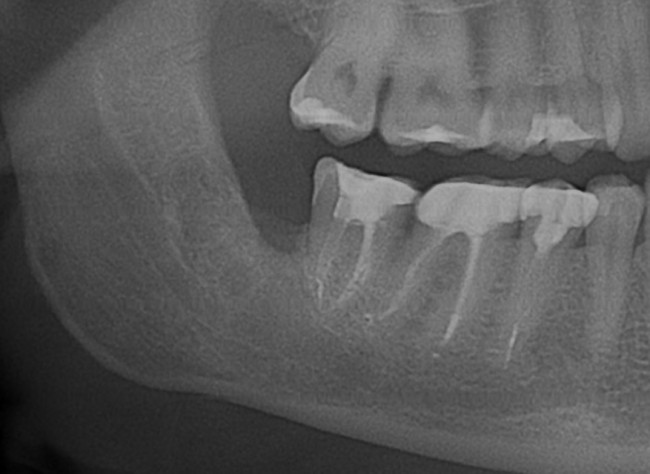

Вот снимок, примерно, через год после удаления.

3

Ни от зуба, ни от кисты не осталось и следа. Чего мы и хотели добиться.